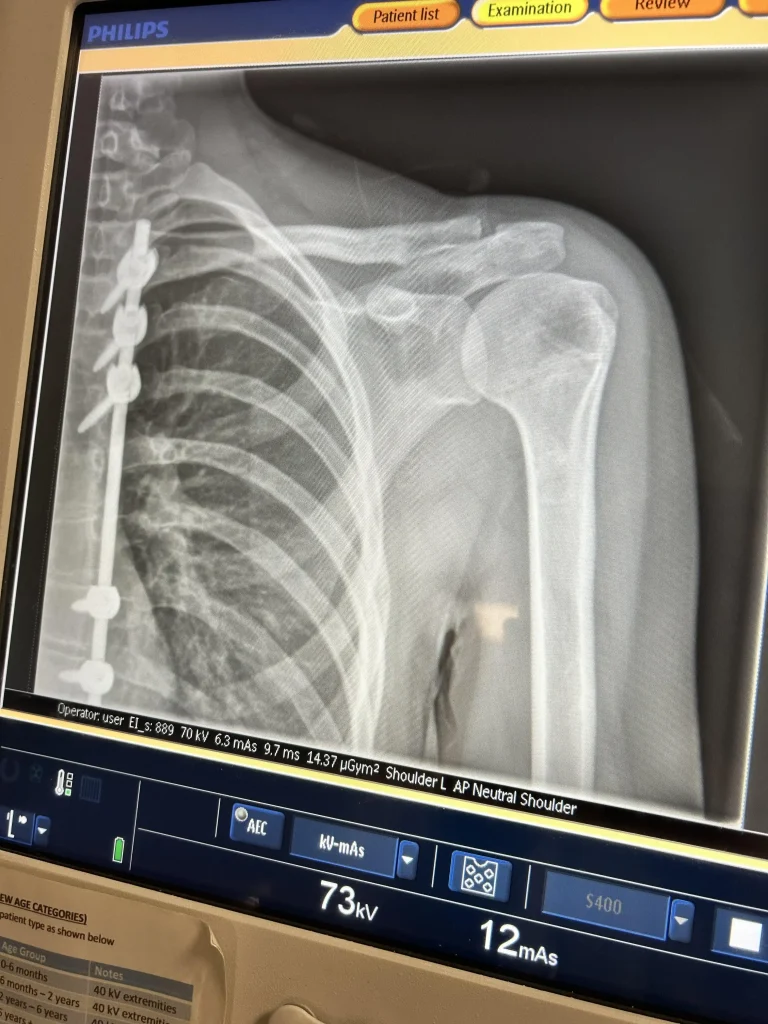

Eva currently has cancer in her bones; specifically in her leg, spine, scapula and hips.

She’s had to undergo surgery to have parts of her ribs and spine removed to extract as much of the disease as possible.